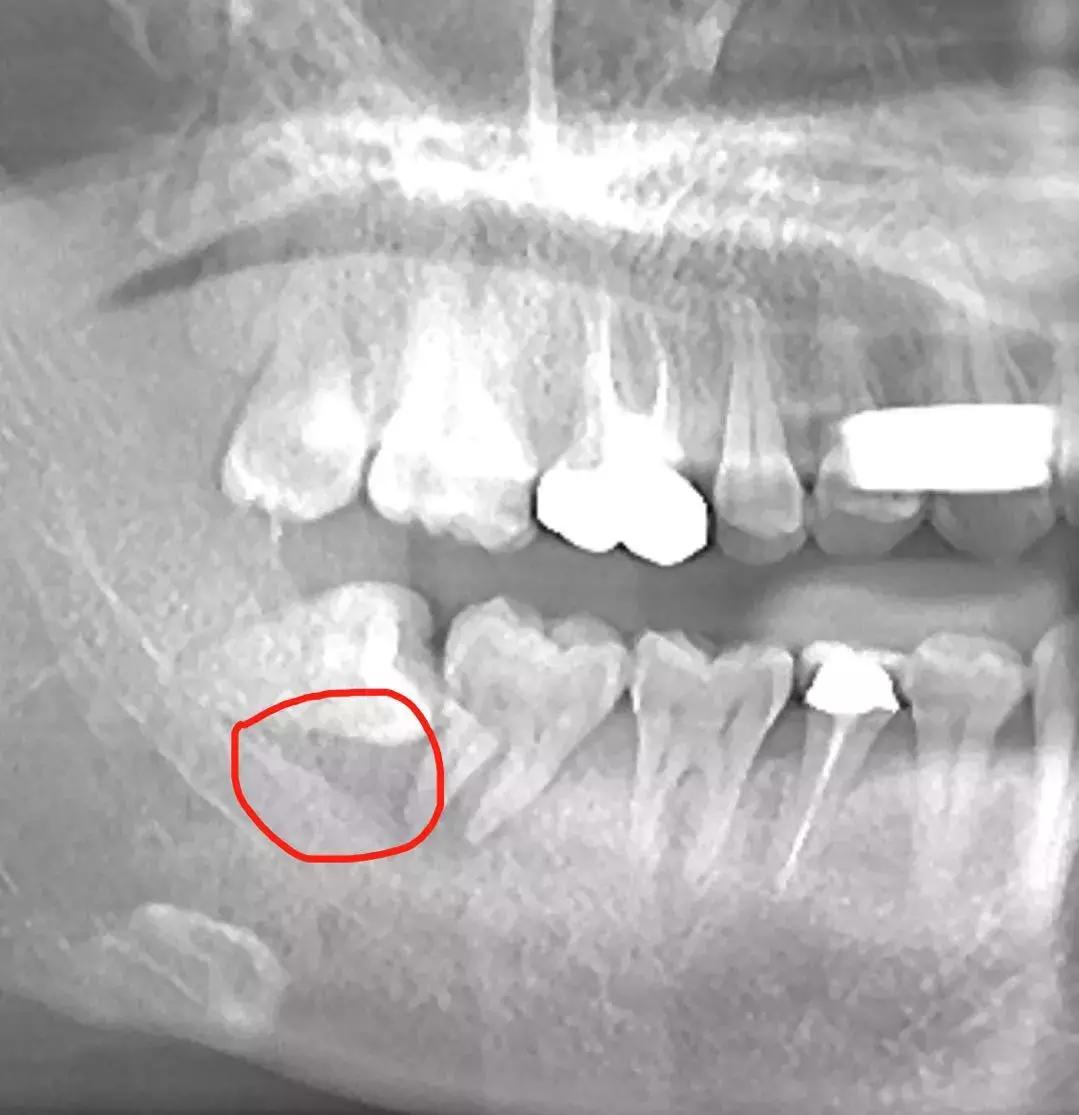

也有一些特殊情况发生,比如拔智齿的

年龄大于25周岁、邻接的第二磨牙远中牙槽骨吸收严重 ,这种考虑局部植骨是有好处的。↓下图红圈内的阴影部分就是已经严重吸收的牙槽骨了